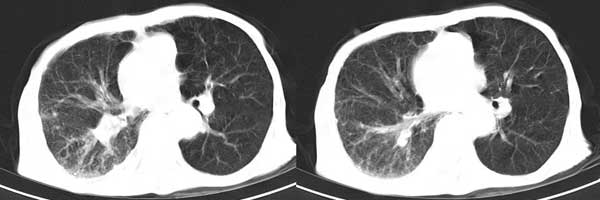

患者男,81岁,咳喘10余年,继往结核病史,发现胸部体表肿物(具体时间不详)就诊

右侧胸廓塌陷。右前上外侧胸壁软组织肿块,其内见有低密度影,肋骨呈溶骨性表现。右肺上叶见大量的间质纤维化表现。右侧膈肌上抬。

患者男,81岁,咳喘10余年,继往结核病史,发现胸部体表肿物

考虑:1、继发性结核,右结核性胸膜炎伴胸壁结核性感染

2、右侧胸壁恶性肿瘤。

肺尖巨大肿块影阴,胸壁受侵肋骨破坏,肿块密度不均且穿破胸壁入皮下,应该是:肺上沟癌;由于肺内有斑片状播散病灶,因此不排除胸壁结核。

患者男,81岁,咳喘10余年,继往结核病史,发现胸部体表肿物。

考虑:1 右侧胸壁恶性肿瘤(多考虑:胸膜间皮瘤)。

2 继发性结核,右结核性胸膜炎伴胸壁结核性感染。